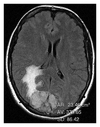

2.3.1. Peritumoral Brain Edema

The peritumoral brain edema index was defined as volume of tumor + volume of edema/volume of tumor. Volume measurements were obtained by using the freehand region of interest (ROI) tool on Kodak Carestream picture archiving and communication system (PACS) (Rochester, NY). After outlining the tumor and the tumor + edema on each slice of the FLAIR sequence a surface area was generated by the PACS (Figure 2). The surface area was multiplied by slice thickness to approximate the volume through that slice and all slice volumes were added to give total volume measurements.